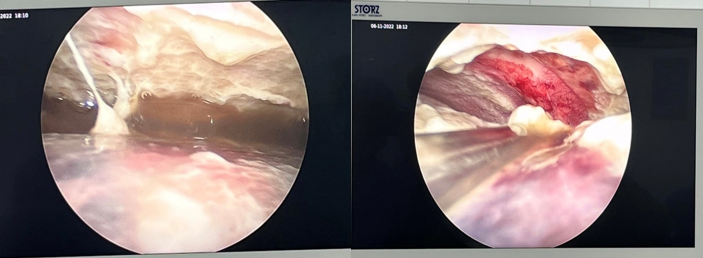

Ngay trong ngày hôm đó trẻ đã được phẫu thuật nội soi bơm rửa, làm

sạch, gỡ dính và đặt dẫn lưu khoang màng phổi. Sau phẫu thuật ngày thứ nhất

triệu chứng sốt và nhiễm trùng giảm rõ rệt, trẻ tỉnh táo, và ăn uống trở lại.

Hình ảnh mủ màng phổi quan sát

trong phẫu thuật nội soi

Mủ và giả mạc gây xơ dính màng

phổi được lấy ra bằng phương tiện nội soi